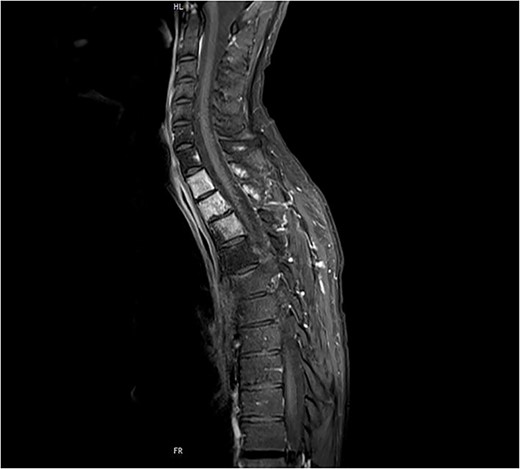

Despite the definitive chemoradiation therapy, a locally progressive tumor without evidence of distant metastasis was detected 2 months later in an MRI associated with the infiltration of Th1–3 and invasion of the first and second left thoracic root without evidence of a myelon compression (Figs 1 and 2).

Preoperative sagittal MRI (STIR) image of patient No. 2 depicting active tumor invasion of T1, T2 and T3 as well as pathological hypodense C7 and Th4 vertebral bodies.